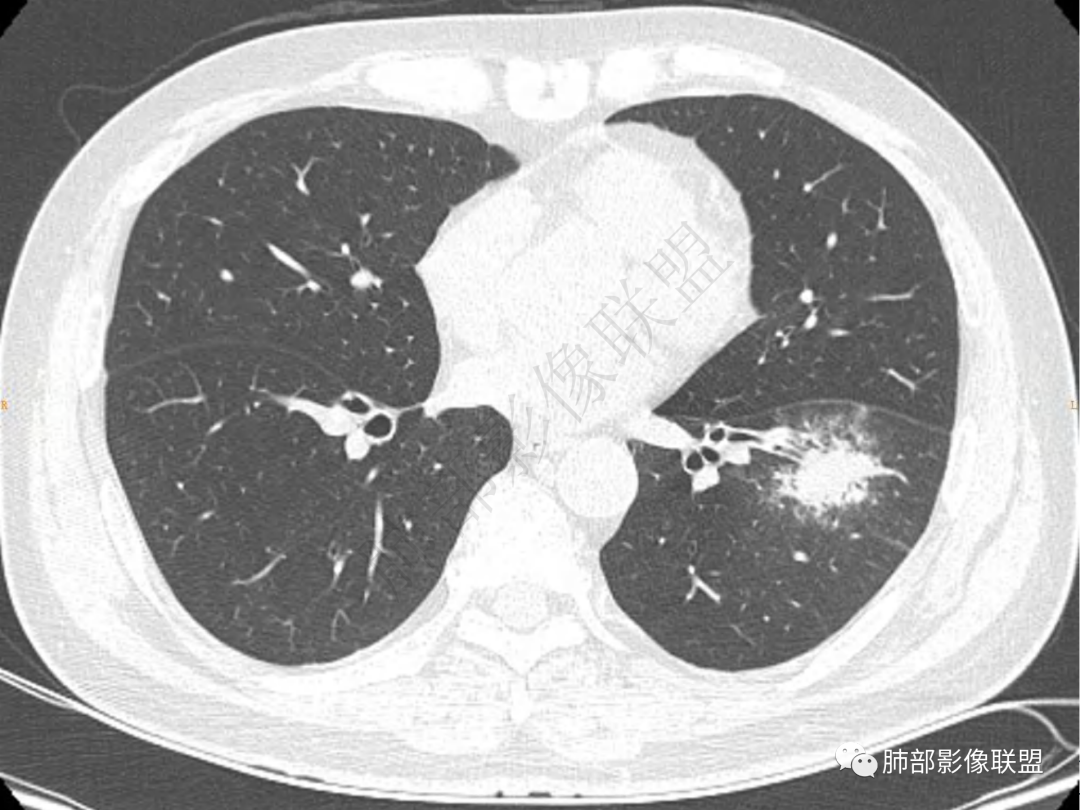

1.中年男性,咳嗽咳痰20余天,间断咯血2周

2.左肺下叶团片影,跨背段及内前基底段,实性部分类椭圆形,密度不甚均匀,可见毛刺及棘状突起,未见典型分叶及胸膜凹陷。病灶上下缘可见相应肺段支气管旁进侧出,管壁轻度增厚,未见狭窄阻塞。

3.周边较大范围磨玻璃影,边界相当模糊,小叶增厚明显。注意叶裂另一侧、左肺舌段亦可见磨玻璃影及增厚的小叶间隔。未见明确卫星病灶。

4.实性部分不均匀环形强化并显示一小范围低密度坏死区或空洞。较之肺窗,整体纵隔窗范围较小,提示病灶并不十分密实。抑或为不同时段图像。

5.双肺门及纵隔未见增大淋巴结。未见胸腔积液。